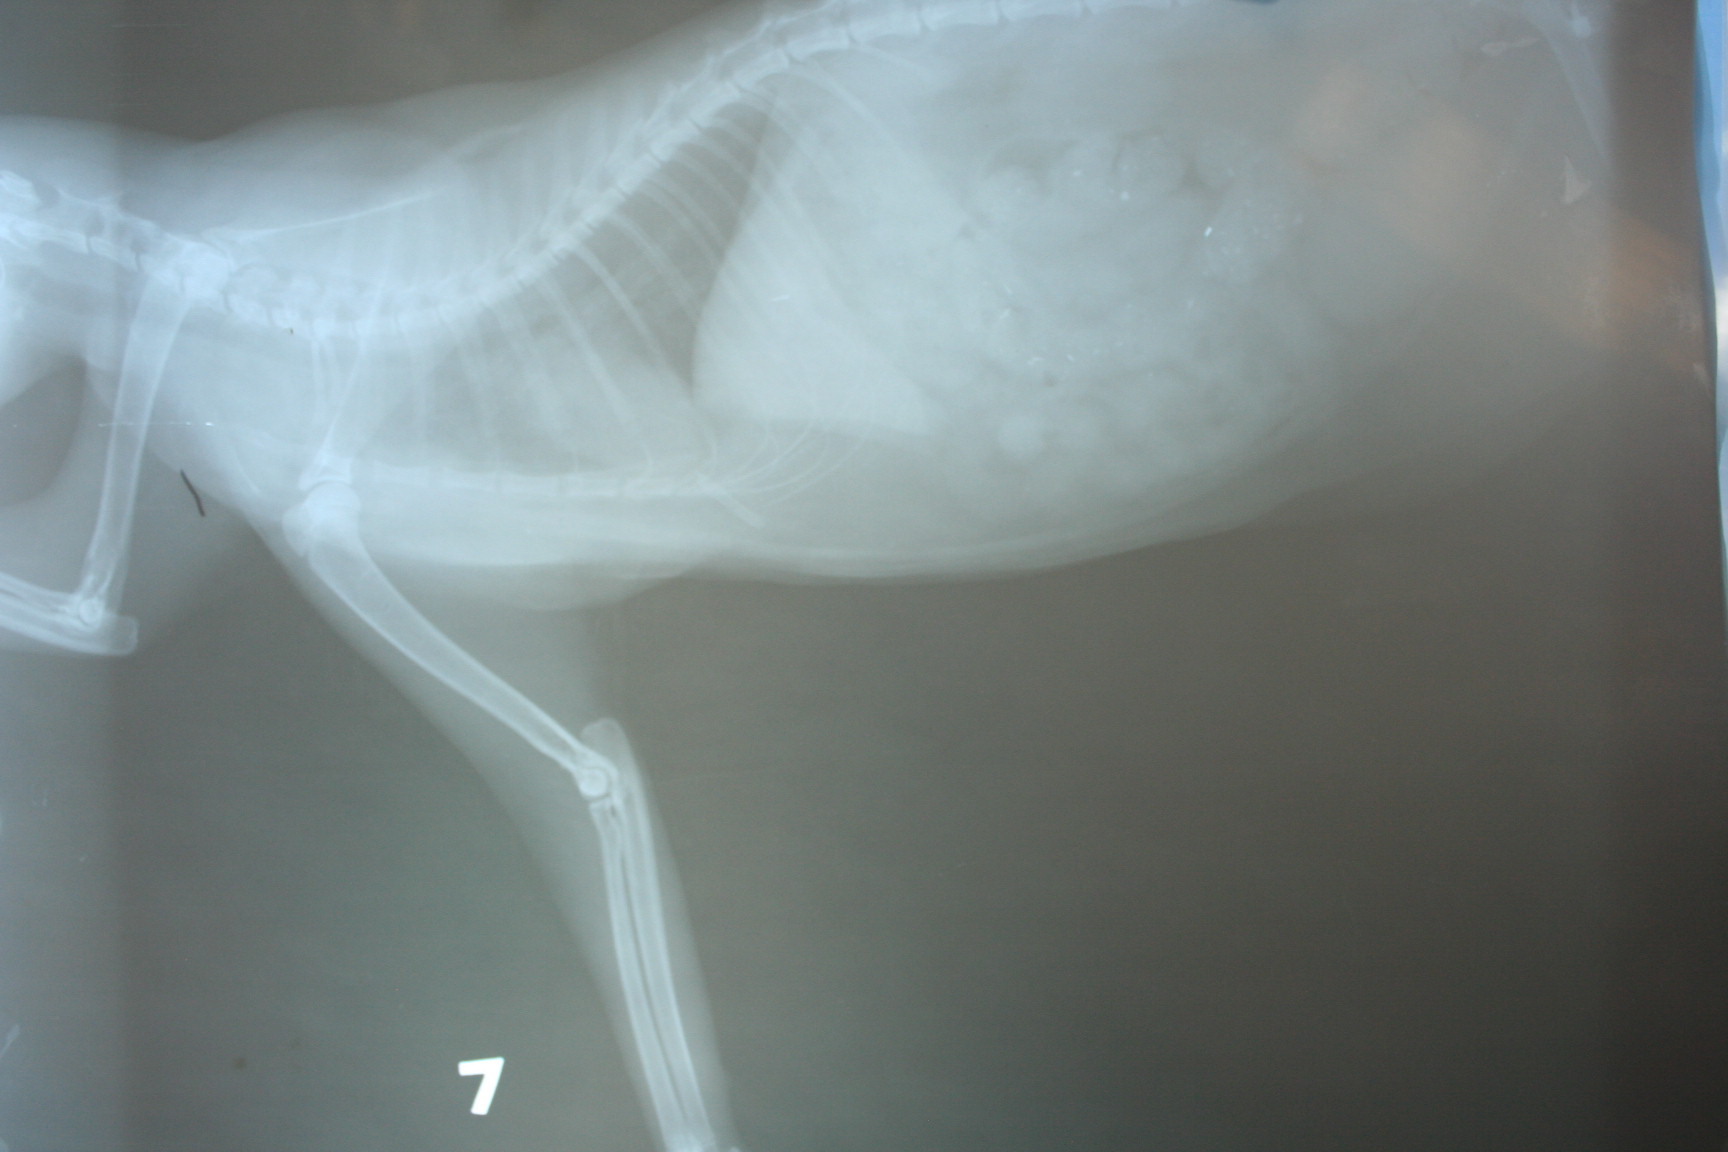

經醫生細心檢查發現,

小朋友除了左前及左後腿跛行外,

她的腳墊只剩一點點.

肌肉及肌腱也有受傷...

2. 10/14 X光片2張 800